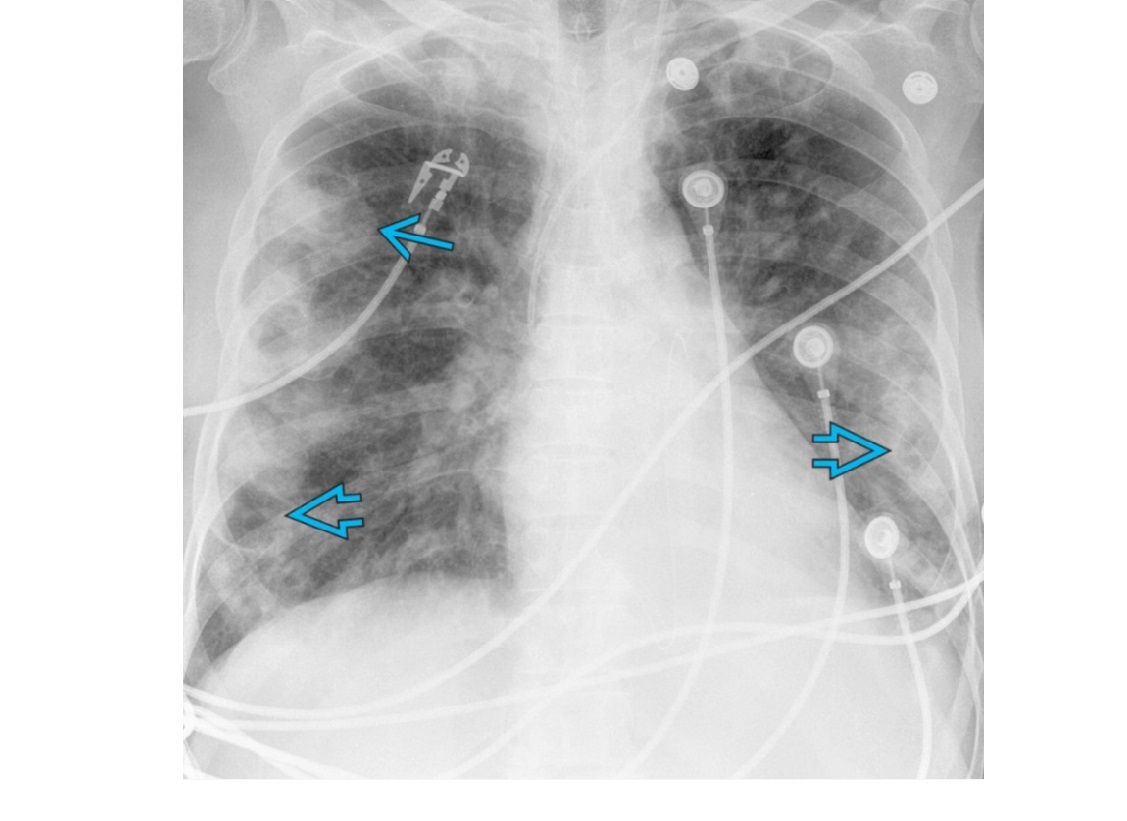

Septic emboli

Peripheral wedges shaped densities +/- cavity

Lower lobe predominant